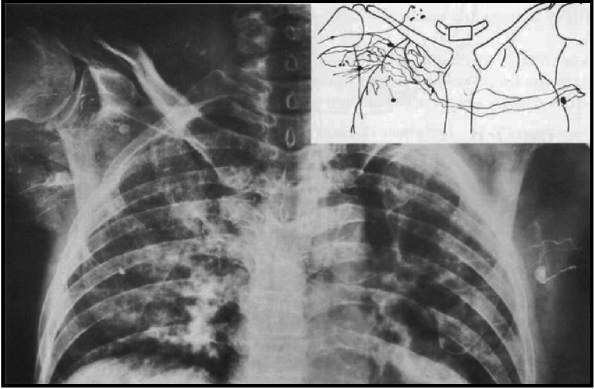

(3)术后胸部伤口常规加压包扎使淋巴液向对侧引流增加,Bobbio等[11]曾报道过类似的情况(图2)。

图2 两侧乳腺区域之间的外部连接[11]